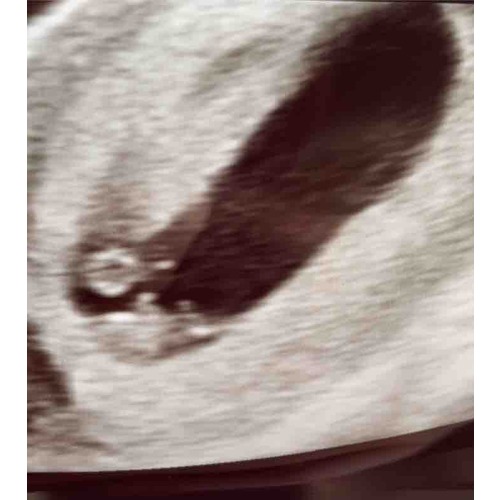

Mijn echo van afgelopen maandag bij 7+4. Helemaal onderin gelegen met het hoofdje rechts, twee ‘stompjes’ die uit moeten groeien tot armpjes. Daarboven het vruchtzakje. Zo bijzonder hoe ze dat allemaal al kunnen zien! Ik ben benieuwd naar de volgende echo.